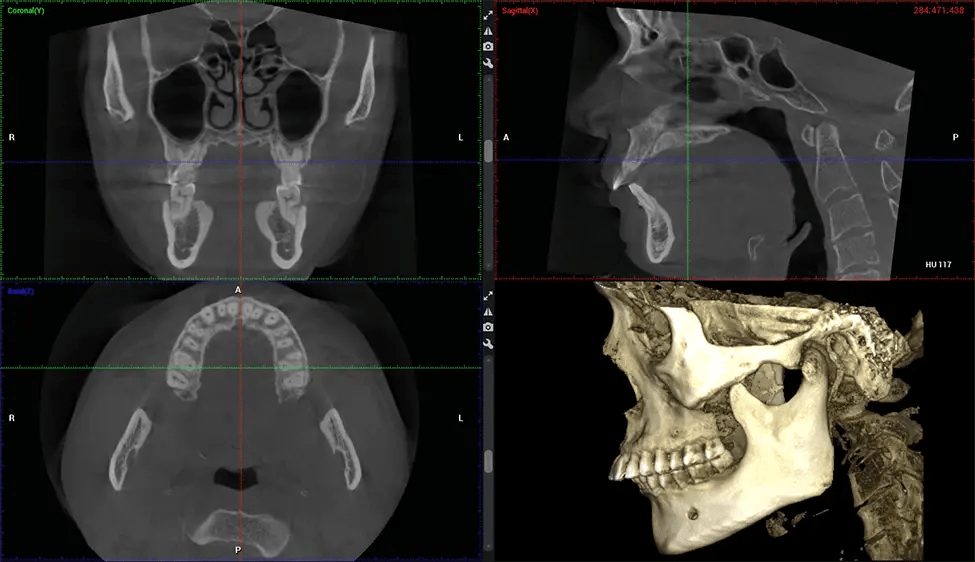

Full Skull to C7 of the Spine

Planmeca Viso G7 CBCT ( Cone Beam CT Scan ) is designed to surpass the demands of industry leaders, specialists, and large institutions. It’s has a large ø25×30 cm sensor with four built-in cameras. It can capture unlimited volume sizes from a ø3×3 cm to a ø30x30cm volume capturing the skullcap through C7 on the cervical spine. The Planmeca Viso G7 offers the industry’s largest single volume scan of ø30×19 cm. It’s poised to handle advanced imaging modalities such as Planmeca ProFace® and Planmeca 4D™ Jaw Motion technology. The occipital head support allows an unimpeded view of facial tissue.

Planmeca is the only manufacturer clinically proven to dramatically reduce patient radiation without sacrificing image quality. Planmeca Ultra Low Dose™ achieves an average reduction in dose of 77% without a statistical reduction in image quality allowing doctors to incorporate 3D imaging into routine protocols with effective patient radiation often lower than 2D intraoral imaging. This increases patient care, allows doctors to diagnose more dentistry, and often earlier in disease progression, than with 2D imaging alone.